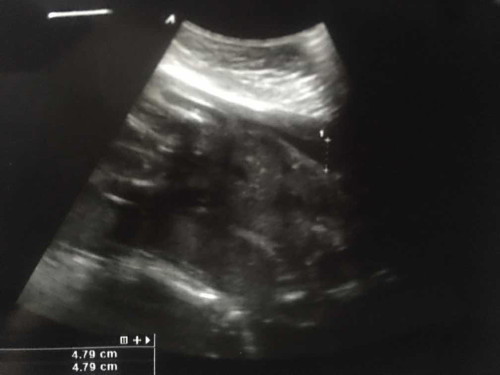

ไม่รู้ว่าหัวเเขนขาน้องอยู่ตรงไหนค่ะ อาจดูตลกที่ถามนะคะ555 เเต่ว่าไม่รู้จริงๆ คือตอนหมอชี้ไห้ดู ก็เห็นเเต่ไม่ได้เห็นชัดมากเพราะเเม่สายตาสั้นค่ะ พอมาดูรูปก็พอเข้าใจในเเบบของตัวเอง ก็กลัวว่าที่เข้าใจมันจะไม่ใช่ เลยจะมาถามๆเเม่ๆที่ดูเป็นค่ะ ว่าน้องสมบูรณ์ไหมคะ #ท้องแรก #ขอคำแนะนำกับแม่ๆด้วยนะคะ #ขอบขคณุล่วงหน้าค่ะ